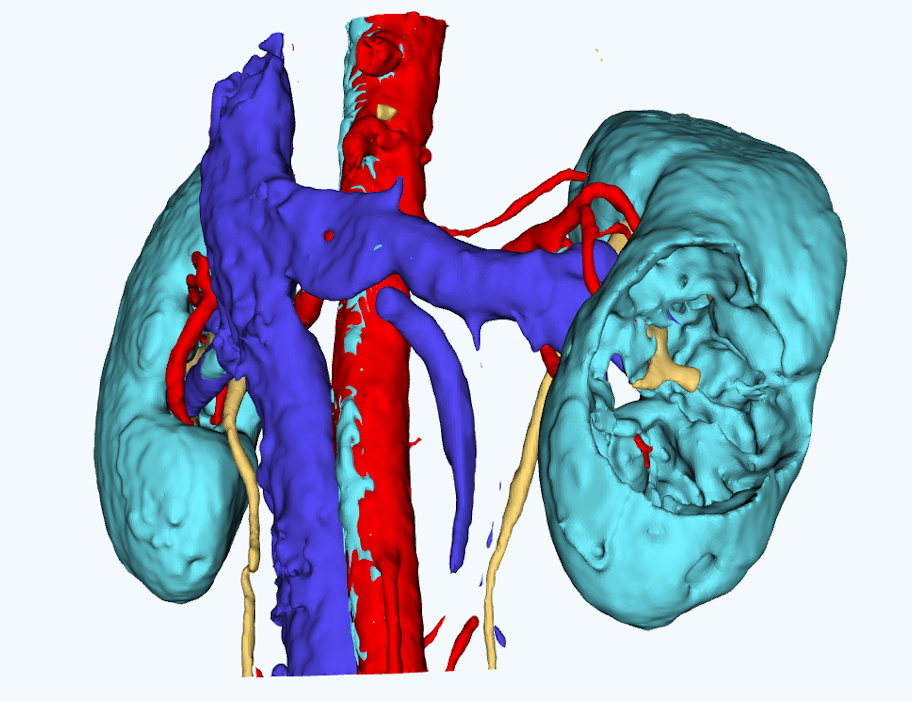

для планирования оперативного вмешательстваСервис создает интерактивные виртуальные 3D модели пациента на основе снимков компьютерной томографии

Персонализированная анатомия

Сервис позволяет выделить расположение артерий, вен, мочеточников, новообразований и паренхимы почки пациента.

Снижение рисков

Сервис позволяет выделить расположение артерий, вен, мочеточников, новообразований и паренхимы почки пациента.Использование сервиса имеет статистически значимое преимущество по времени выполнения операций, по времени тепловой ишемии, по величине кровопотери

Работа с 3D моделью

Врач может работать с 3D моделью для изучения анатомических особенностей пациента